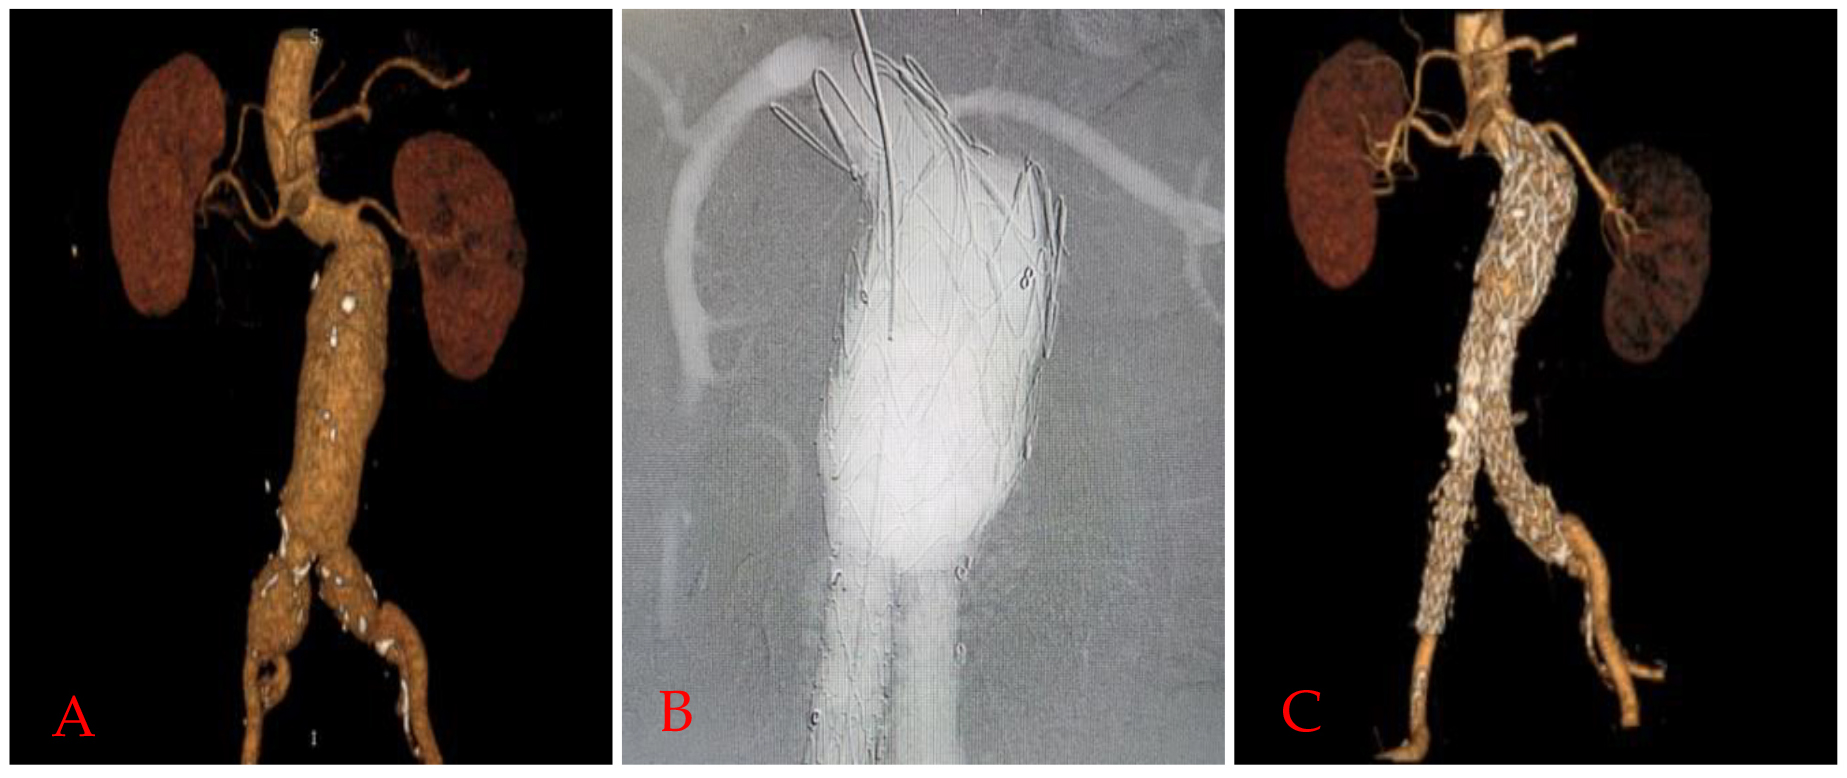

One patient also had a contained rupture in the thoracic segment. There was a heavy thrombus burden in 5 patients circumferentially involving nearly 25-50% of the neck (Fig. 2A,B).

Fig. 2.Remodeling of thrombus and true lumen in the aneurysm after Funnel EVAR. Preoperative thrombus burden at the infrarenal neck (A) and postoperative diminished thrombus burden and enlarged active lumen with no infrarenal neck enlargement at 48 months CTA control (B). EVAR, endovascular aneurysm repair; CTA, computed tomographic angiography; AAL, aortic active lumen; LRA, left renal artery.

Wide necks over 28 mm tend to have more Type Ia endoleaks and require late interventions [2, 3, 4]. Patients with wider proximal aortic necks also have shorter necks and larger aneurysm diameters. This may be the reason for the higher morbidity rates. We think that the most complex issue for this technique is placing the endograft at the diseased aortic segment. In the ageing aorta, there is ongoing aneurysmal disease as the aortic wall structure is negatively altered in a progressive manner. In our experience, we did not face any neck enlargement and no aneurysm-related complications. Tassiopoulos et al. [19] reported that small necks appear to be at higher risk for subsequent dilatation whilst matching the size of the endograft. Amongst the different Funnel-EVAR techniques, although it depends on the availability of the endograft sizes, using a longer thoracic endograft may create the possibility of sideway movements and result in Type III endoleaks [10, 12, 16]. Using aorto-uni-iliac endografts may alter the patency of extra-anatomic bypass grafts [8]. After standard EVAR, AND may develop with an incidence of 20–28% at two years and up to 43% after open surgical repair [17, 18, 19, 20]. Ongoing aneurysmal disease or the radial force of the oversized endograft may be the reason for this complication. No neck enlargement was demonstrated in our midterm follow-up period (Fig. 2A,B).

Ectatic aortic necks also frequently have a thrombus burden. In our experience, a thrombus did not influence the technical success of EVAR. We did not perform any ballooning procedures to the thrombus at the infrarenal neck. The thrombus was probably thinner and diminished in the CTA controls because of radial force, and we called it the “pillow effect” (Fig. 2A,B). Close monitoring is mandatory in the presence of neck thrombus due to concerns regarding embolization. Shintani et al. [21] reported that neck thrombus did not affect the incidence of Type Ia endoleak or migration. However, it was significantly associated with thromboembolic complications such as distal embolization and renal dysfunction [21].